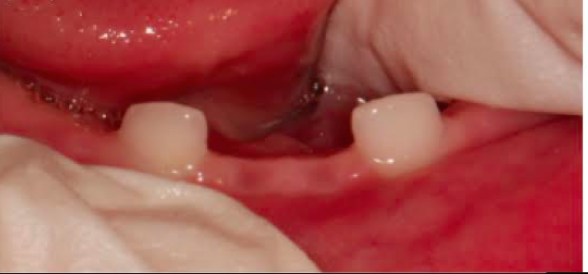

4) Διαταραχές οδοντοφυίας και ατελή οδοντογένεση ορατές ήδη από τη βρεφική ή παιδική ηλικία, πρόωρη απώλεια νεογιλών ή ενήλικων δοντιών, σοβαρή τερηδόνα.

Τέλος, η οδοντοϋποφωσφατασία περιλαμβάνει πρόωρη απώλεια νεογιλών δοντιών και / ή σοβαρή τερηδόνα (εικόνες 8, 9). Σπάνιες περιπτώσεις βρεφών με υποφωσφατασία που έχουν φυσιολογική δράση αλκαλικής φωσφατάσης στον ορό θεωρούνται ότι πάσχουν από «ψευδοϋποφωσφατασία».